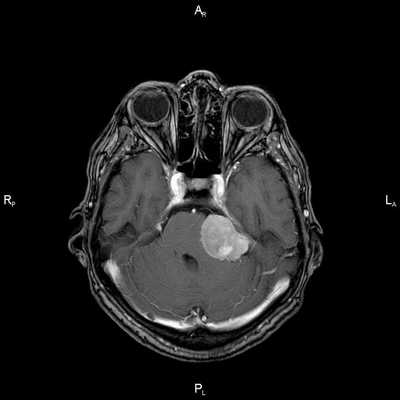

Пациент Р. 62 лет

Проблема: жалобы на частые головные боли, снижение слуха (левое ухо), а также шум в ушах (больше слева). Пациент был направлен на МРТ головного мозга в ЦМРТ с целью уточнения диагноза.

Диагноз: Онкология. Менингиома мосто-мозжечкового угла

При МРТ головного мозга в левом мосто-мозжечковом углу определялось больших размеров округлой формы внемозговое патологическое образование, с четкими ровными контурами, широким основанием, прилежащее к твердой мозговой оболочке. После внутривенного контрастирования отмечалось равномерное, выраженное усиление интенсивности МР-сигнала от вышеописанного образования, а также твердой мозговой оболочки. Пациенту был поставлен диагноз (менингиома левого мосто-мозжечкового угла).